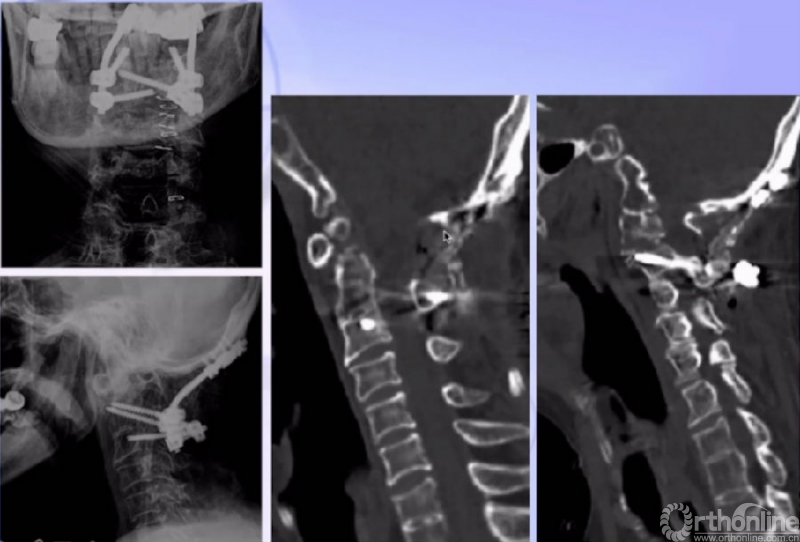

术后CT

单一后路:松解+复位+融合

后弓切除减压 经后路侧块松解

复位、内固定